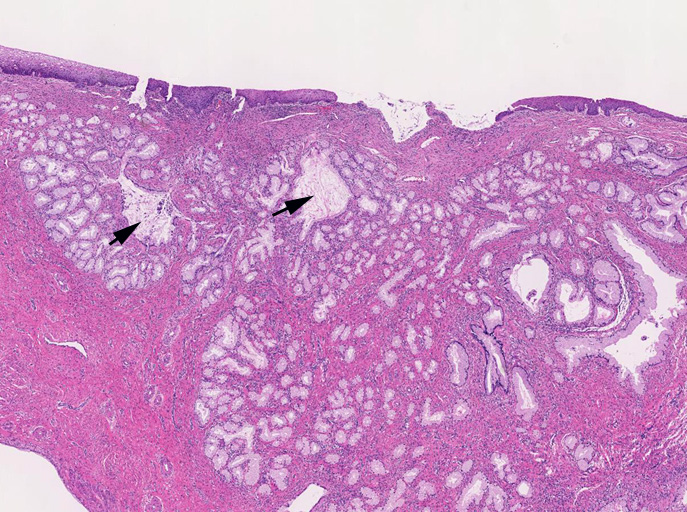

しかしながら完全に異型がないとはいえず分葉構造を保持しているものの上皮の内腔への乳頭状増殖や重層化, 軽度から中等度の核腫大, クロマチン増加, 核分裂像をしめす腺が認められる---> with atypia

間質の一部には炎症細胞浸潤がめだつ。間質浸潤を疑う「折れ釘-->いびつなおれ釘のようなねじれた--」のような不整な形態の腺管は認められない。

LEGHは大型導管に類似した拡張腺管の周囲に中型から小型の腺管が分葉状に増生するのが特徴。小型腺管を構成する高円柱上皮細胞質は正常頸管腺上皮の細胞質が淡明あるいは, やや青白い色調を呈するのに対し淡明ないし淡好酸性となる傾向にある。

loupe像では, 拡張した導管を中心に高円柱上皮からなる腺管が分葉状に配置する所見が認められる。